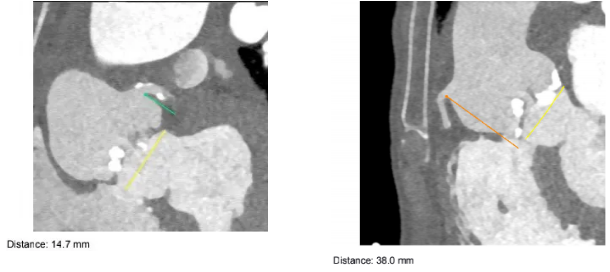

患者CT结果显示:主动脉瓣属于Type0型二叶瓣,重度狭窄并钙化,整个主动脉段非常扭曲,且在胸主动脉段有严重缩窄合并巨大主动脉瘤,双侧下肢动脉入路狭窄。同时,患者术前心脏超声提示心功能值(EF)仅17%,手术风险极高,国内外并无可供参考的手术方案和经验分享。